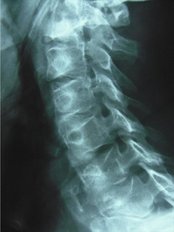

Experience holistic healthcare at Chiropractic and Complementary Medical Centre, where we have been providing safe and friendly Chiropractic, Acupuncture, and Herbal Medicine services for over 25 years. Our highly skilled and experienced practitioners offer an integrated healthcare approach to address your specific needs and provide effective treatments for a wide range of conditions. Whether you're seeking relief from headaches, back pain, anxie... (Show more)